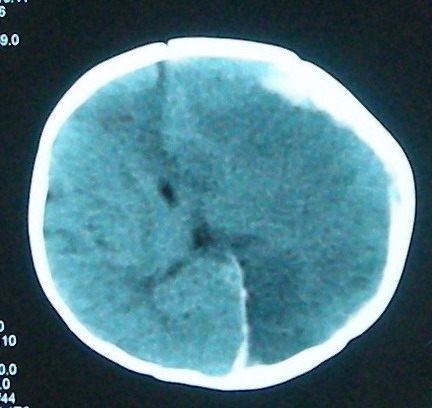

左侧大脑半球和右侧额叶大片低密度影,脑沟及外侧裂池消失,左侧脑室闭合,考虑脑梗塞伴有水肿。

考虑:1、左额颞顶慢性硬膜下血肿(可能为产伤所致);

2、蛛网膜下腔出血;

3、左侧大脑半球及右额叶脑肿胀、梗塞(缺血性脑梗塞为脑疝所致)。

结合临床考虑1、脓毒栓子致左侧大脑半球及右侧额叶梗塞。2、左侧额颞顶部硬膜下血肿形成.3、镰下疝形成。

左额颞顶慢性硬膜下血肿(可能为产伤所致);蛛网膜下腔出血,已明确,至于左侧大脑半球大片低密度影并脑组织肿胀,考虑:梗塞导致缺血缺氧性改变.至于梗塞原因随诊观察吧!

左侧大脑半球和右侧额叶大片低密度影,脑沟及外侧裂池消失,左侧脑室闭塞,左侧蛛网膜下腔片絮状高密度影,结合病儿高热、脑膜刺激征(+),考虑:炎脑,脑水肿,左侧蛛网膜下腔出血。至于出血原因,应该为高热所致维生素c需要量增加,而补给不足所致维生素c缺乏,抑或是使用抗惊厥药影响维生素k代谢,使凝血发生障碍而出血。当然,一切都是猜测,需要临床进一步检查验证。